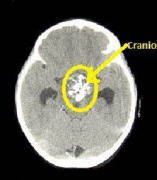

顱咽管瘤CT能發(fā)現(xiàn)嗎?癥狀表現(xiàn)會(huì)同時(shí)出現(xiàn)嗎?

顱咽管瘤CT能發(fā)現(xiàn)嗎?癥狀表現(xiàn)會(huì)同時(shí)出現(xiàn)嗎?顱咽管瘤是一種起源于垂體柄附近殘留的胚胎組織的良性腫瘤,它們通常生長(zhǎng)緩慢,但由于其位置不同,靠近大...